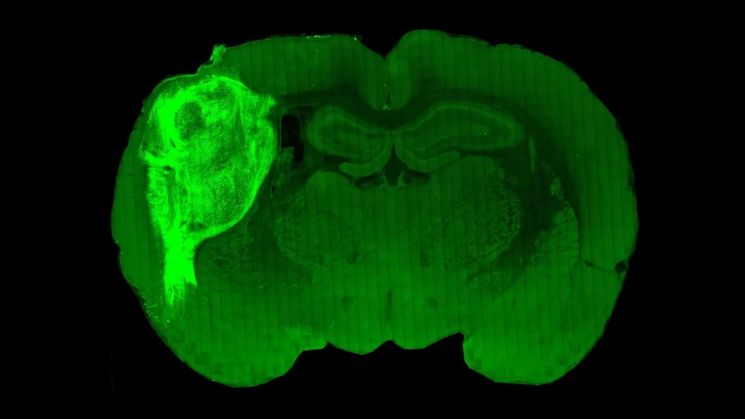

인간 줄기세포로 만든 뇌 오가노이드를 이식한 쥐의 뇌. 사진 출처=미국 스탠퍼드대

14일 국제학술지 네이처에 따르면, 미국 스탠퍼드대 연구팀은 지난 12일 인간의 줄기세포를 이용해 만든 뇌세포를 시궁쥐(rats)의 뇌에 이식해 작동하게 만드는 실험에 성공해 이 학술지에 논문을 게재했다. 연구팀은 인간 뇌 오가노이드를 쥐의 뇌 체성감각 피질(somatosensory cortex), 즉 수염이나 다른 감각 조직으로부터 신호를 전달받아 그것을 해석하는 다른 부위로 전달하는 조직에 이식했다.